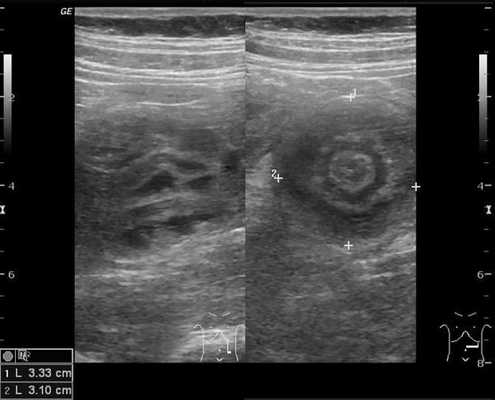

Для визуализации инвагината проводится УЗИ брюшной полости: определяется гипоэхогенное образование с участком гиперэхогенности в центральной части. Также может применяться ультразвуковая допплерография с целью оценки кровотока в сосудах брыжейки. Обзорная рентгенография брюшной полости обладает меньшей чувствительностью при обнаружении инвагината, но применяется как скрининговый метод исследования при острой боли в животе с целью исключения перфорации, обструкции.

Золотым стандартом считается проведение ультразвукового исследования (сонографии) органов брюшной полости, так как оно является неинвазивным, быстрым, безопасным, безболезненным и высоко информативным методом. [9] [10] При помощи сонографии можно диагностировать инвагинат не только на типичных, но и на атипичных участках кишечника, что повышает точность установления и верификации диагноза.

В момент УЗ-исследования врач может определить один из симптомов:

- симптом мишени (за счёт внедрения одной кишки в другую инвагинат на срезе выглядит как мишень);

- симптом "почки с завоздушенным центром".